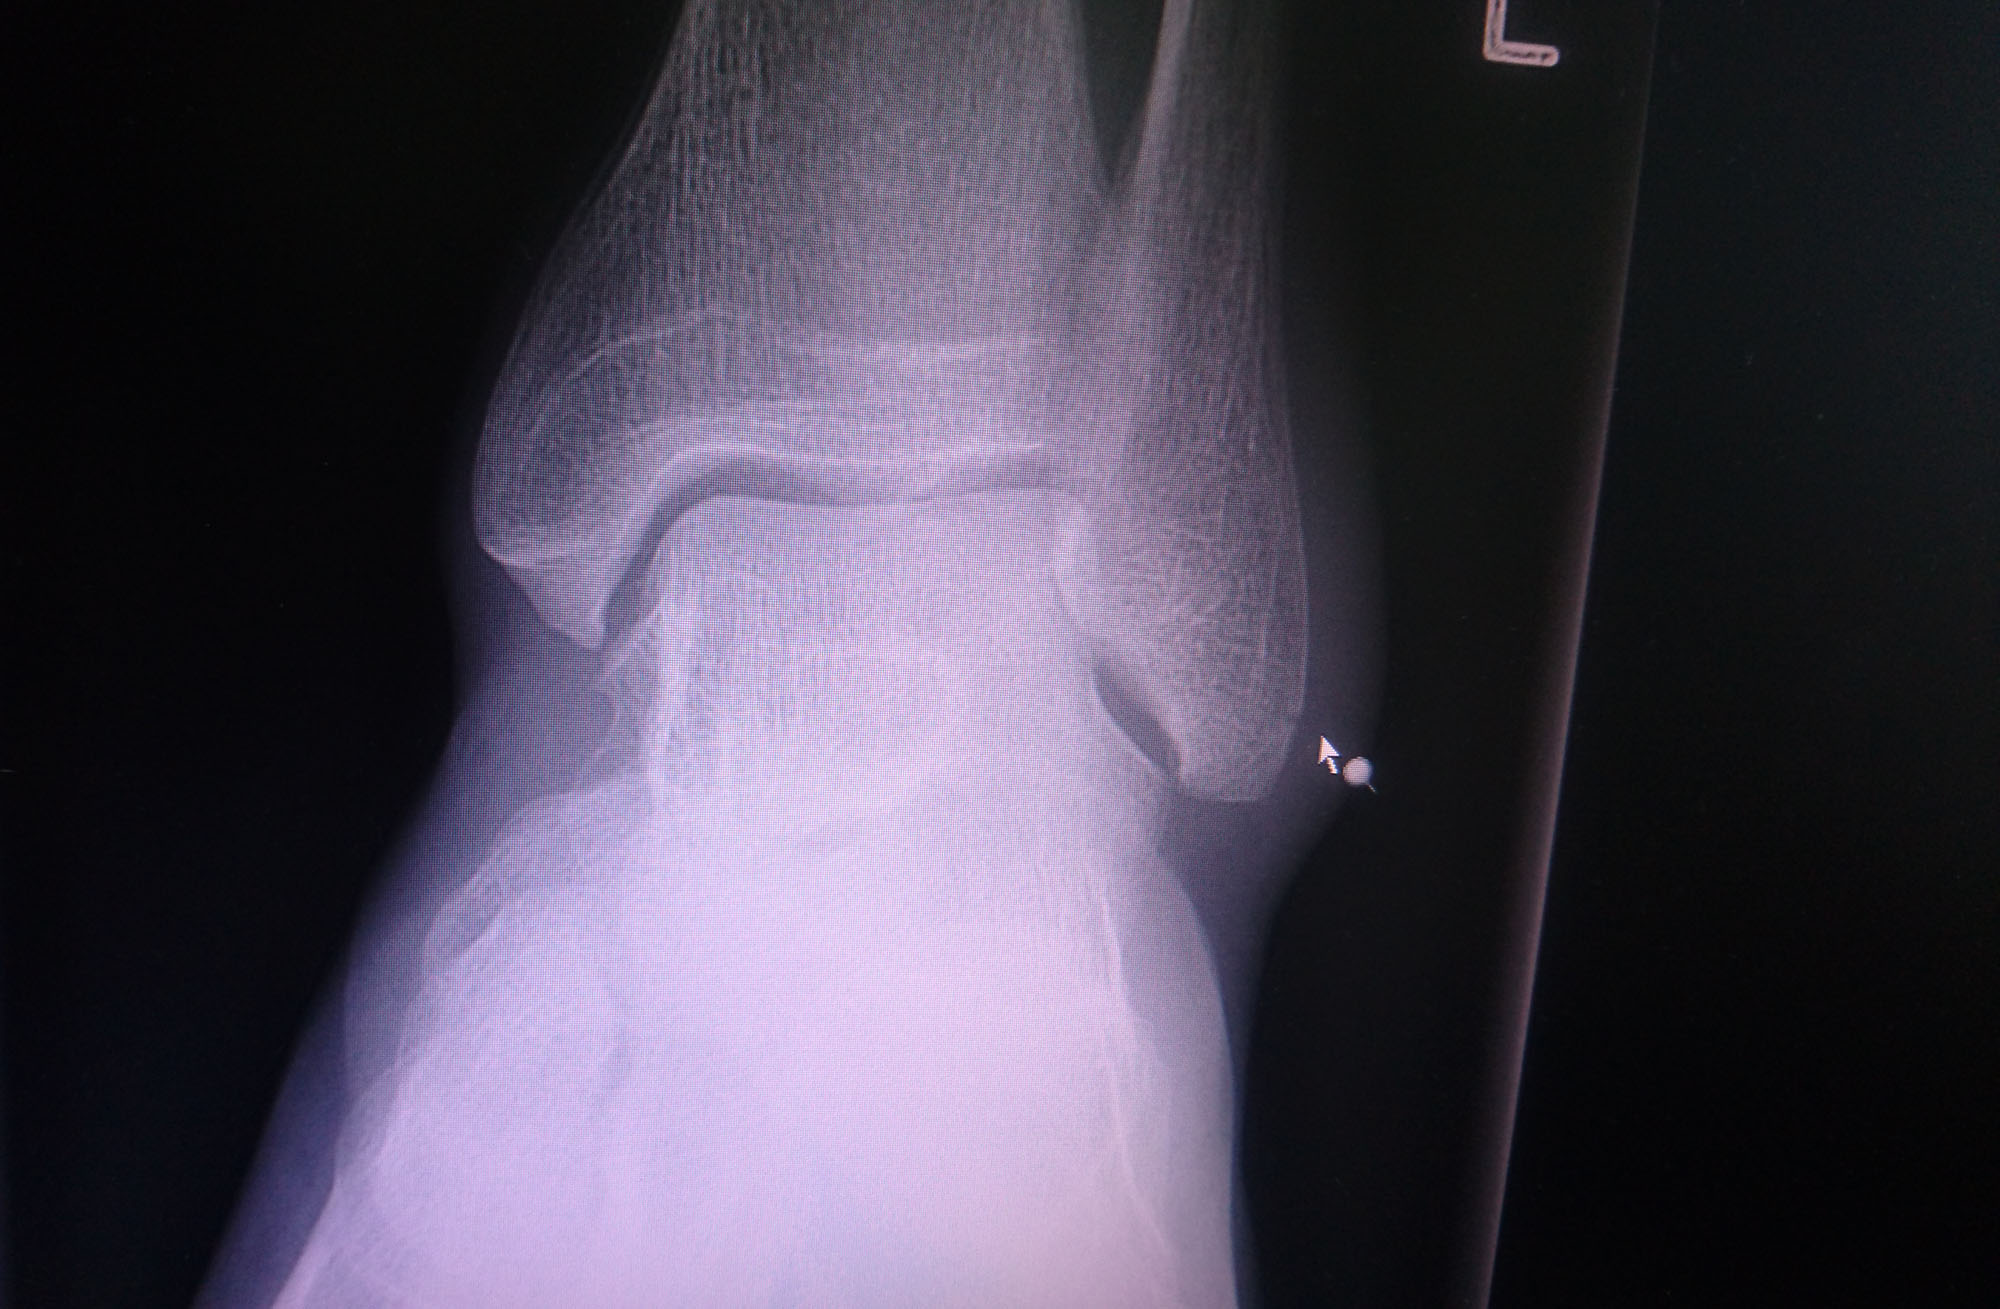

Jeg hade været i garagen og monteret nye dæk på fælge, skiftet olje og filter på motorcyklen og lavet andre småjusteringer. Alt så ok ud i venten på løbet, men det sku ikke være så simpelt mente jeg alligevel, fordi jeg besluttede at vælte med min gadecykel på parkeringen og brække noget i min venstre ankel. Røntgen på Gentofte Hospital viser at det er enden på fibula-knoglen der er brækket. Fuck!

Det er den der knogle der stikker ud ved ankeln. Det heldige er at det ikke er Tibia-knoglen der støtter hele vægten når man står på foden. Så jeg kan stå på foden, men jeg kan ikke vride eller vippe med foden udan at det gører ont som ind i helvede. Alle muskler og sener der ordner balance, vridning og vipning af fode er nemlig fastgjort til Fibula-knoglen der er brækked. Det bliver svært at komme op på, og af motorcyklen, og lige så svært at skifte gear!